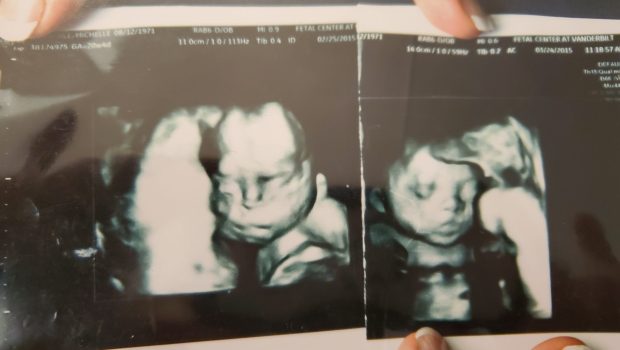

Zobaczcie zdjęcia udostępnione przez rodzinę uzdrowionego chłopca:

Ta niewiarygodna wręcz historia rozpoczęła się ostatniego dnia 2014 roku, kiedy Michelle Schachle, oczekując narodzin dziecka, wybrała się na rutynowe badanie USG. Zdjęcie pokazało coś niepokojącego – lekarka Michelle oznajmiła, że dziecko ma zespół Downa.

Później przeprowadzono kolejne badania, aż 25 lutego 2015 r. okazało się, że nienarodzone maleństwo cierpi na śmiertelną puchlinę wodną, objawiającą się niekontrolowanym gromadzeniem się płynu. Daniel wspomina, że ginekolog nie dawała żadnych szans na urodzenie żywego dziecka. Jako lekarka z ponad 30-letnim doświadczeniem pracy w zawodzie nigdy jeszcze nie widziała takiego ciężkiego przypadku tej choroby.

Przed podróżą do Fatimy małżonkowie udali się na kolejne badanie USG, chcąc potwierdzić, że Michelle może podjąć taki wysiłek. Lekarze zezwolili na to, choć na zdjęciu widać było, że w płucach i głowie dziecka zgromadziło się wiele płynu.

Matka chłopca powiedziała jej wówczas, że na wcześniejszym badaniu klatka piersiowa nienarodzonego dziecka była opuchnięta jak balon z powodu nagromadzonego płynu. Jego małe płuca były mocno ściśnięte, a pozostałe organy wewnętrzne wydawały się zanurzone w olbrzymiej ilości płynu. Twarz była nienaturalnie opuchnięta i chłopiec w łonie matki wyglądał jak nadmiernie otyły mężczyzna. Po powrocie z Fatimy wszystkie te oznaki ustąpiły, zauważa Daniel.